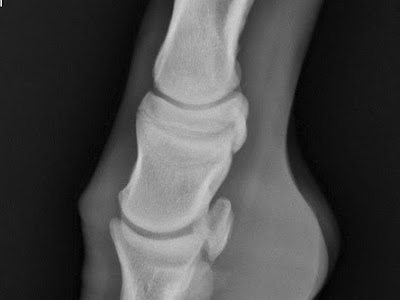

The radiograph below is from a weanling colt with a severe case of a "club foot" Figure 1 is the affected foot and figure 2 is th...